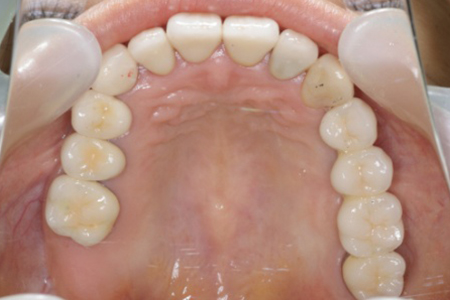

インプラントで噛み合わせの再構成を伴った症例。

治療後のメンテナンスを行わないと

周囲炎になるリスクあり。